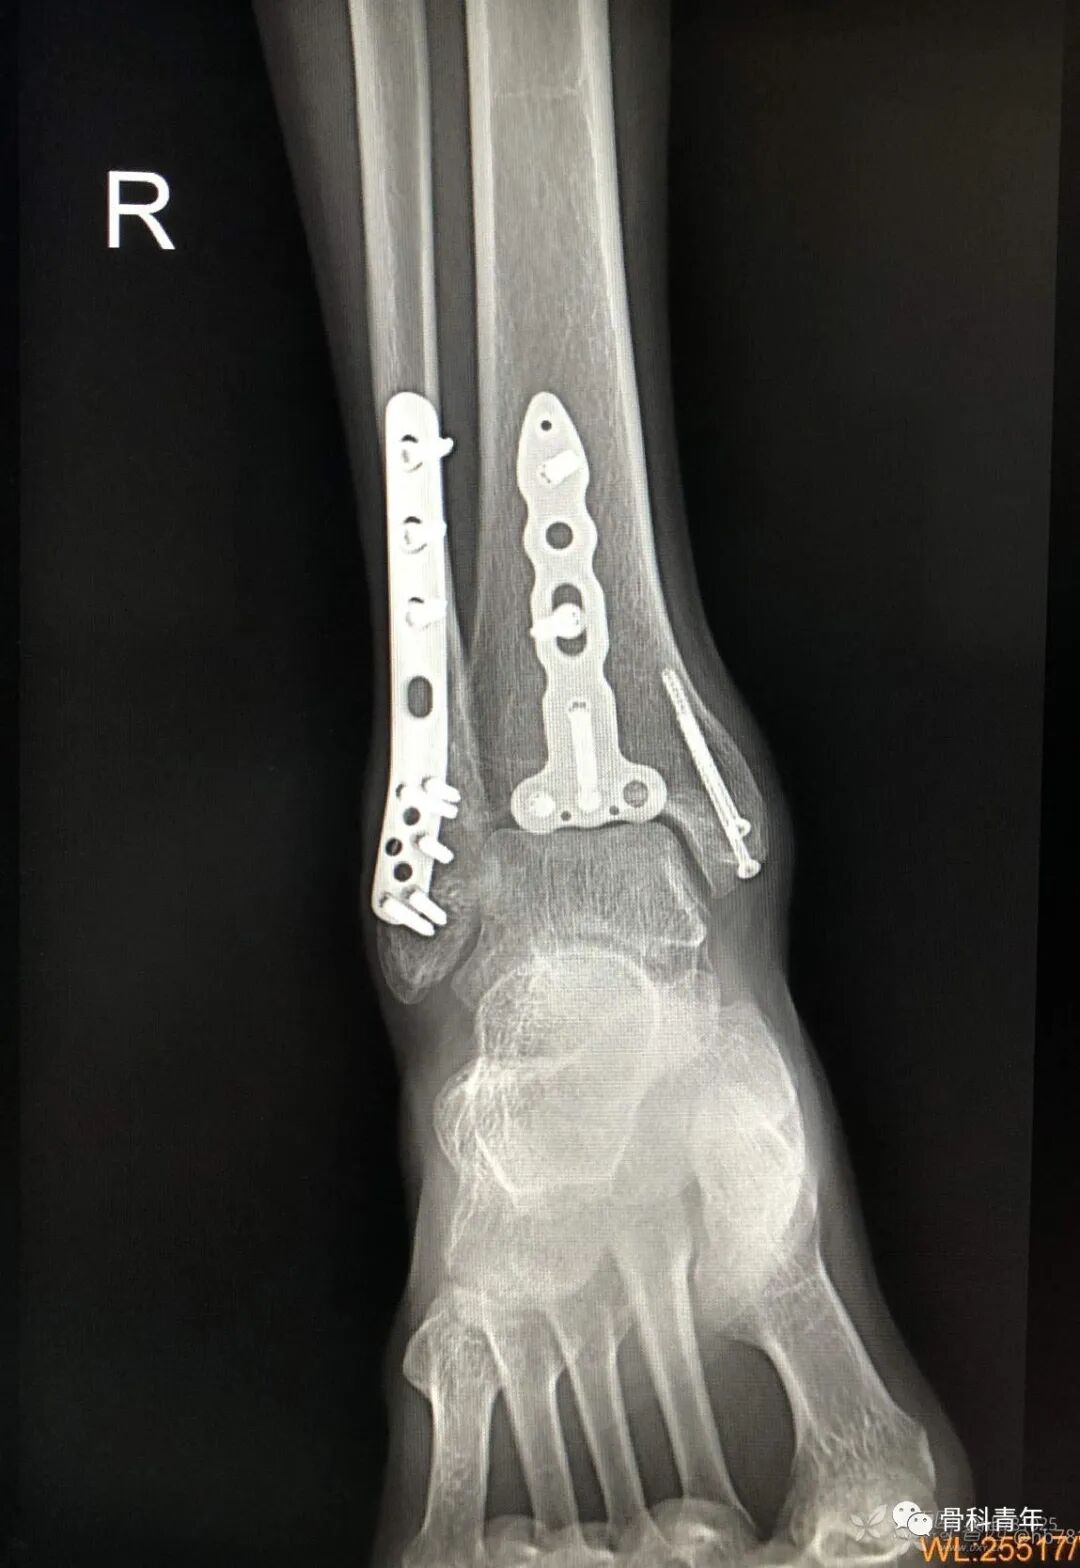

11.胫骨下段伴内踝骨折

12.三踝骨折